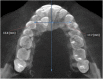

Methods: A cross-sectional study (split mouth design) that included 28 CBCTs (i.e., 56 sides) with unilaterally impacted maxillary canines was performed. After conducting a pilot test to gauge the researcher, heights and widths of skeletal and dentoalveolar variables obtained in the maxilla were measured using coronal and axial views. The angulations of incisors were also measured, and the side with impaction and the unaffected side were compared. Paired sample t test and Wilcoxon signed-rank test were used.

Results: Significant statistical differences (2 mm, p < 0.001) were found between the impacted and non-impacted side measurements from the mid-palatine raphe to the first premolar (proximal alveolar bone crest between the canine (deciduous or permanent) and first premolar); the distance were significantly lower (12.72 ± 2.25 mm) than in the side without impaction (14.67 ± 2.00 mm). Also, the central and lateral incisor angulations showed significant reductions; presenting disto-angulated incisors on the impacted canine side (86.14 ± 7.70° and 74.75 ± 12.67°, respectively) and mesial-angulated incisors on the non-impacted side (91.63 ± 6.79° and 81.21 ± 8.56° respectively). The other skeletal and dentoalveolar measurements showed no significant differences.

Conclusions: The width from the median raphe to the first premolar is lower in the side of maxillary palatal impacted canines than in the side without impaction. Lateral angulations of incisors were disto-angulated on the side of impacted canines. Both conditions have clinical implications in the orthodontic treatment.